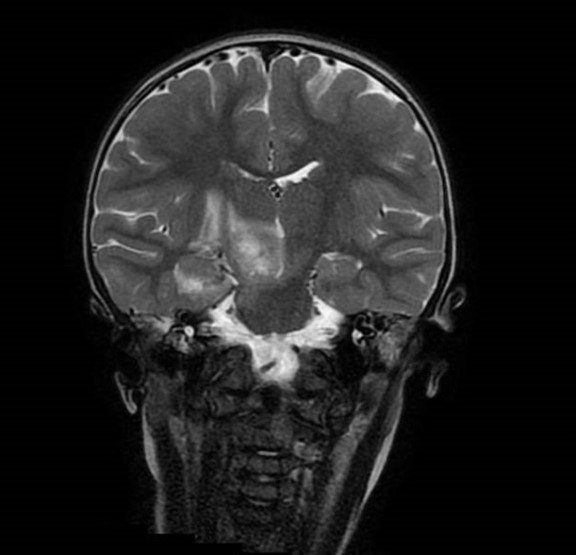

Se realiza resonancia magnética (RM) cerebral, que evidencia lesión mal definida de unos 3,1 × 3,6 cm, heterogénea, hiperintensa en T2 y flair con algunas calcificaciones puntiformes, centrada en pedúnculo cerebral derecho con carácter expansivo. Extensión caudal hacia protuberancia y paramedial izquierda hacia pedúnculo cerebeloso superior derecho. Se extiende también al tálamo derecho. alcanzando el brazo posterior de la cápsula interna, hipocampo y uncus derecho, con afectación corticosubcortical. Presenta mínimo edema perilesional, provocando engrosamiento parcial en la región derecha del quiasma óptico. Produce discreto efecto de masa con parcial obliteración ventricular.